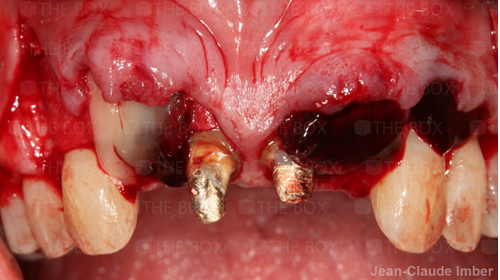

A new case was made public by Jean-Claude Imber check it out here.